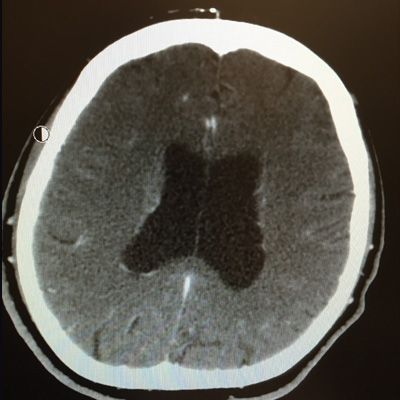

Communicating Hydrocephalus, for common pathologies such as Normal Pressure Hydrocephalus (NPH), post subarachnoid hemorrhage, meningitis or Traumatic Brain Injury (TBI) are treated with Ventriculoperitoneal Shunt placement using Antibiotic Impregnated Catheters and Programmable Valves. Endoscopic Third Ventriculostomy (ETV) is done for cases of Obstructive Hydrocephalus, such as in Aqueductal Stenosis or Pineal Region or Tectal Tumors.The use of Antibiotic Impregnated shunt catheters has made a significant impact in decreasing the incidence of shunt infections. Also, the use of Programmable Valves has provided a very usefull noninvasive method of changing and adjusting valve pressures for optimal drainage rate.